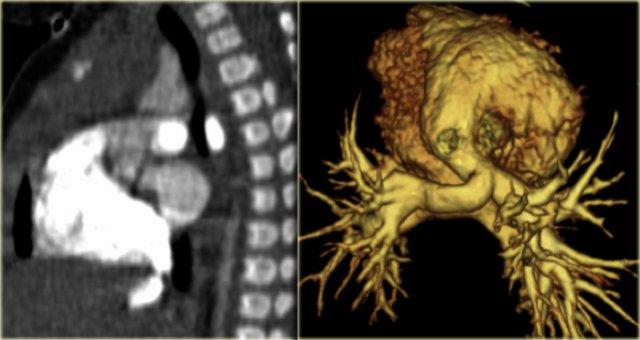

On the left the reconstructions demonstrating a double aortic arch.

There are branches coming off the right arch and branches coming off the left arch.

The right arch is typically larger and higher than the left.

There is a complete ring that encircles the esophagus and the trachea and usually there is stridor or dysphagia.

Two brachiocephalic arteries arise on each side separately (four vessel sign).

On the left axial images and posterior view of volume rendered reconstruction.

Describe the findings and then continue.

The findings are:

- four vessel sign

- double arch

- right arch higher and larger

- esophagus and trachea are completely encircled

The narrowing of the trachea is seen on the axial images, but better appreciated on the MPR and Volume Rendered image.

On the left preoperative and postoperative MDCT studies of a 2-month-old female infant with double aortic arch presenting with stridor and repeated apnea.

The smaller left arch is partially resected.